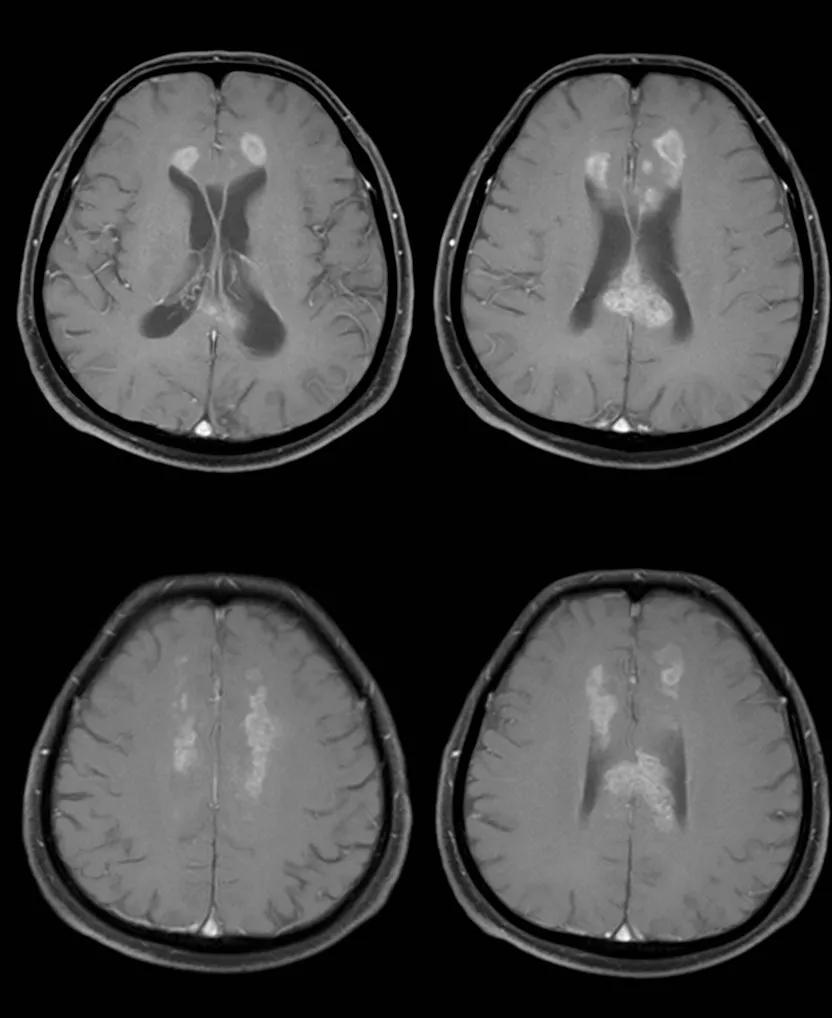

- 急性期表现为胼胝体弥漫性肿胀,T1WI呈稍低信号,T2WI及FLAIR呈稍高信号,以矢状位观察最佳,可单独累及胼胝体压部或整个胼胝体,DWI呈高信号,ADC图呈低信号,部分患者可观察到脑室周围白质或内囊受累,少见皮层受累,表现为扩散受限,不强化和强化病例均可见到。如果增强扫描可见胼胝体有不同程度强化,呈小灶状或不规则斑片状,系血脑屏障破坏所致(如本例),本例患者处于急性期。

48岁,男性,长期饮酒过量20年,出现出现眩晕,胼胝体、侧脑室周围白质、内囊后肢对称性异常信号,扩散受限,诊断为原发性胼胝体变性急性期。

胼胝体压部病变及多发皮层对称性病变,表现为扩散受限

- 随着病变进展至亚急性期和慢性期,胼胝体内可出现坏死、囊变,以膝部及压部表现为著。在膝部和体部常表现为中心夹层状异常信号,类似“三明治”状,其境界清楚,据认为这是本病的特点之一。病理检查证实,病变主要对称性侵及胼胝体的中心层,而背、腹层面的组织结构相对完好。主要的组织学所见为脱髓鞘,少突胶质细胞明显减少,而含脂巨细胞大量增多。部分病例在T2加权像上,偶见胼胝体变性、坏死区内出现极低信号,镜下病理显示含脂巨细胞内可见散在或成堆的含铁血黄素分布,可能为T2异常低信号的病理基础。